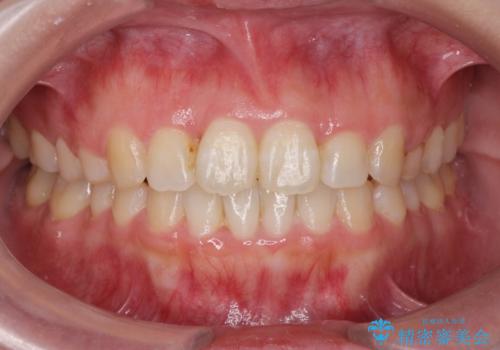

クリーニング(PMTC)掲載症例数554件

最新 クリーニング(PMTC)症例